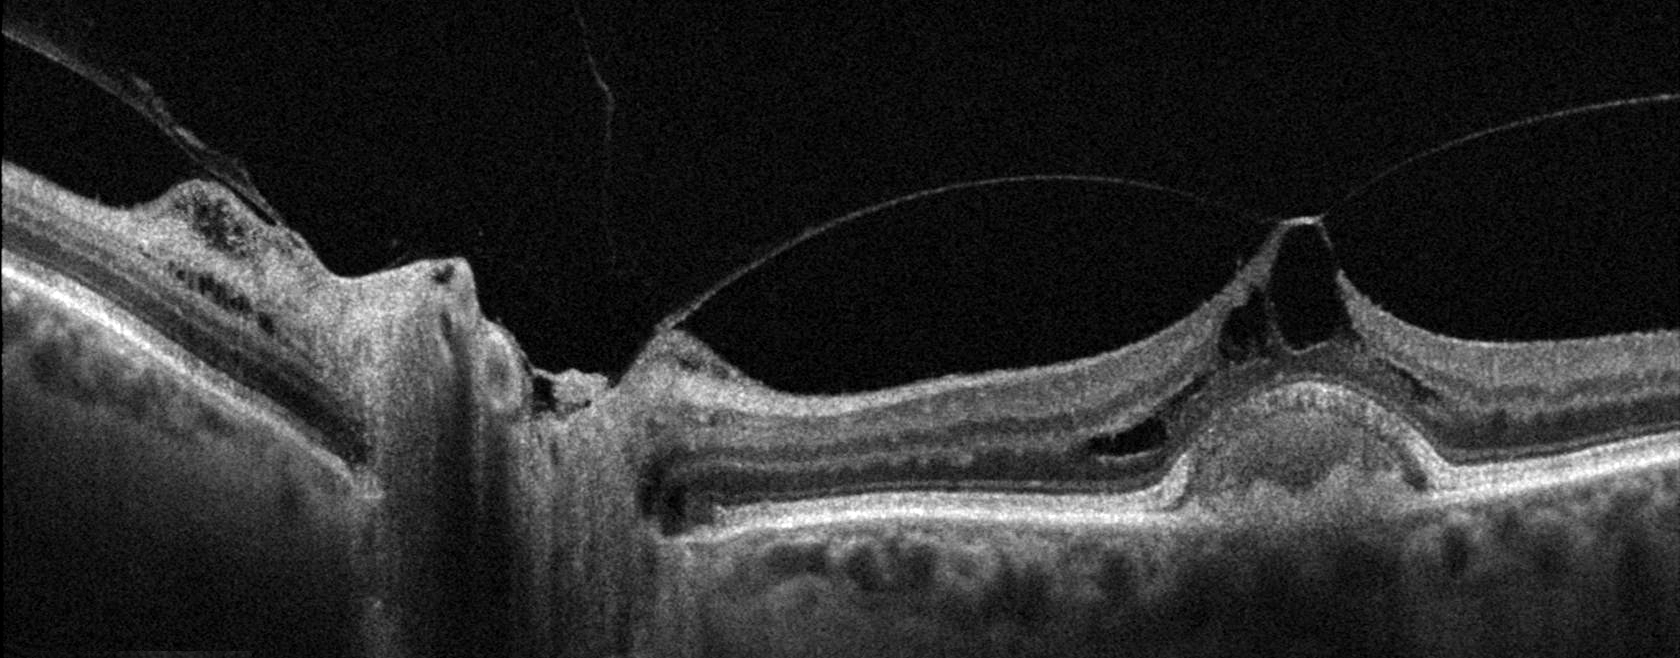

Published inVitrectomy for Vitreomacular Traction Syndrome